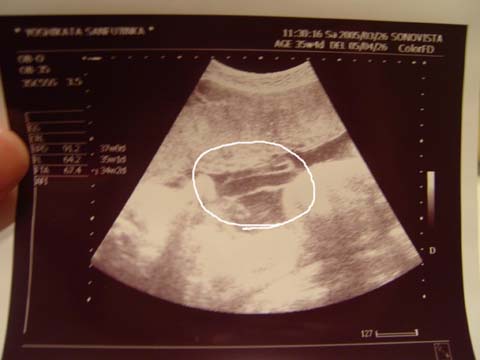

今日の検診で先生がへその緒の写真を撮ってくれました。中央の丸囲みの中、とぐろっぽくなってるところ、わかりますか?